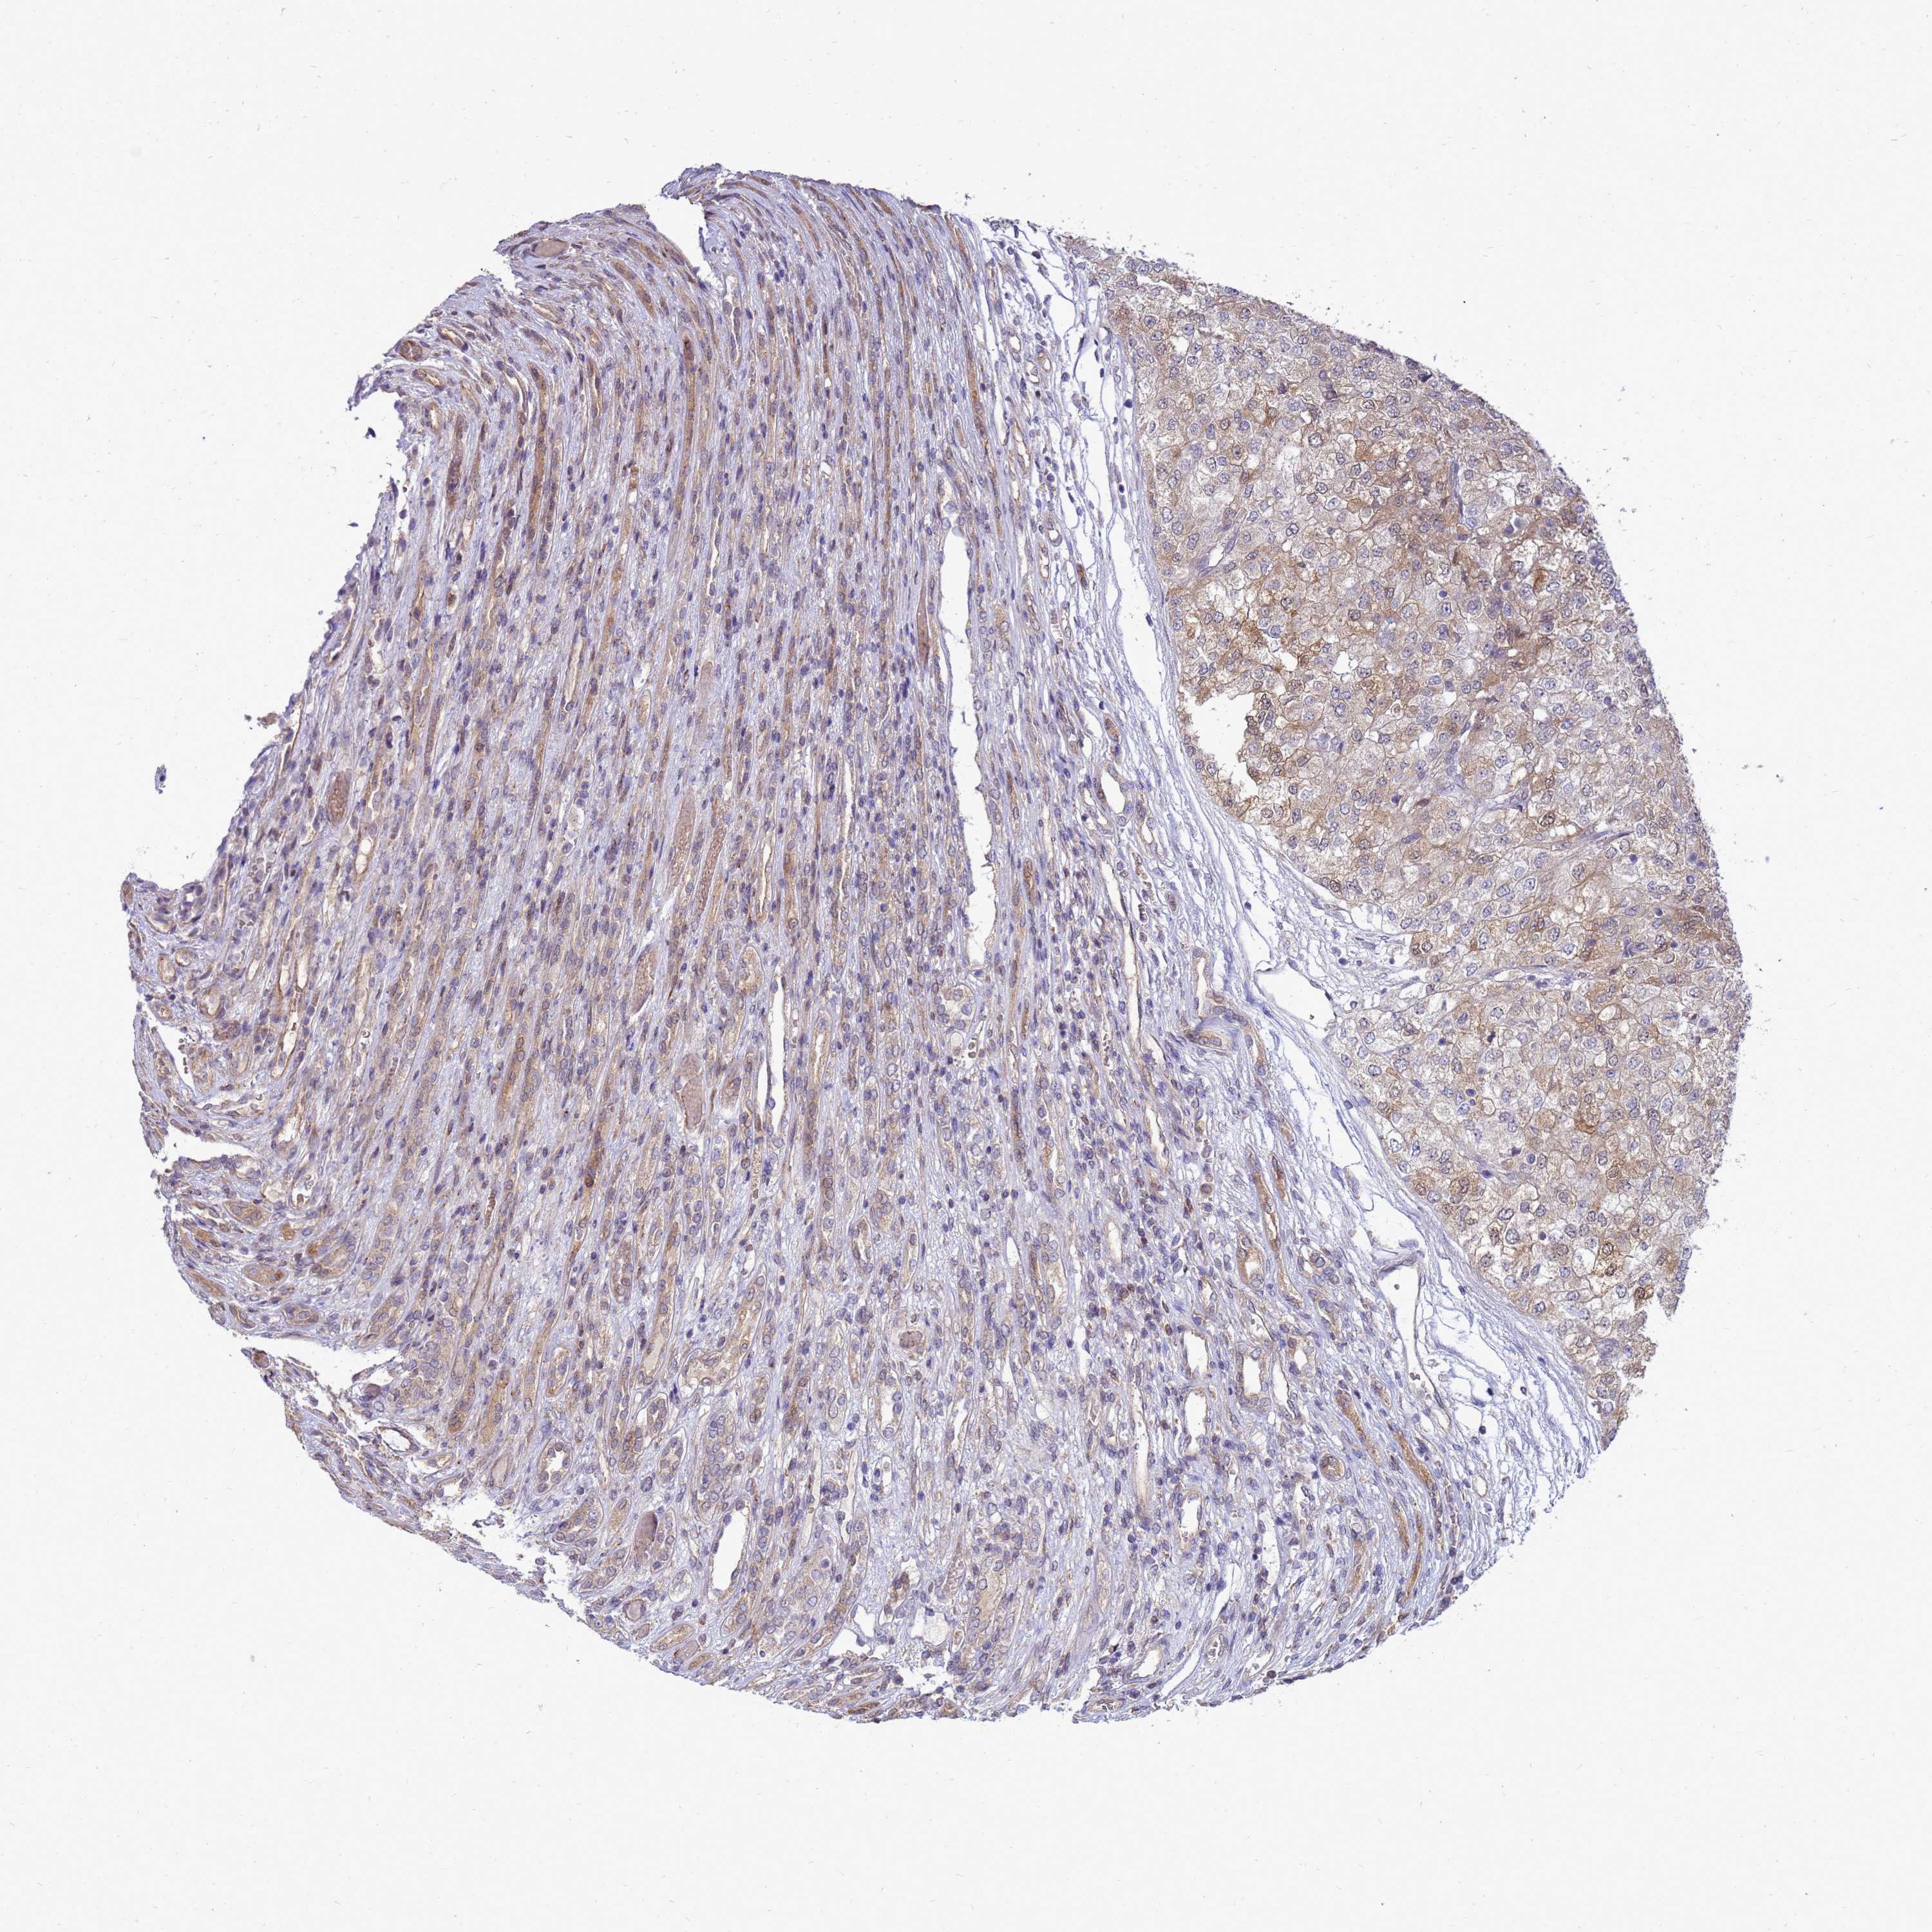

KIDNEY RENAL CLEAR CELL CARCINOMA (TCGA) - Interactive survival scatter ploti

The Survival Scatter plot shows the clinical status (i.e. dead or alive) for all individuals in the patient cohort, based on the same data that underlies the corresponding Kaplan-Meier plots. Patients that are alive at last time for follow-up are shown in blue and patients who have died during the study are shown in red.

The x-axis shows the expression levels (FPKM) of the investigated gene in the tumor tissue at the time of diagnosis. The y-axis shows the follow-up time after diagnosis (years). Both axes are complimented with kernel density curves demonstrating the data density over the axes. The top density plot shows the expression levels (FPKM) distribution among dead (red) and alive patients (blue). The right density plot shows the data density of the survived years of dead patients with high and low expression levels respectively, stratified using the cutoff indicated by the vertical dashed line through the Survival Scatter plot. This cutoff is automatically defined based on the FPKM cutoff that minimizes the p-score. The cutoff can be changed by dragging the vertical line or by entering a cutoff value in the square labeled "Current cut-off".

Under the Survival Scatter plot the p-score landscape (black curve; left axis) is shown together with dead median separation (red curve; right axis). Dead median separation is the difference in median mRNA expression between patients who have died with high and low expression, respectively. It is calculated as follows: median FPKM expression of dead patients with high expression - median FPKM expression of dead patients with low expression. This is intended to aid the user in visually exploring custom cutoffs and the associated p-scores and dead median separation.

Individual patient data is displayed and can be filtered by clicking on one or more of the category buttons on the top of the page. Categories describing expression level and patient information include: high, low, alive, dead, female, male and tumor stages. The scale of the x-axis can be toggled between linear and log-scale by clicking on the "x log" button. Mouse-over function shows TCGA ID, patient information and mRNA expression (FPKM) for each patient.

& Survival analysisi

Kaplan-Meier plots summarize results from analysis of correlation between mRNA expression level and patient survival. Patients were divided based on level of expression into one of the two groups "low" (under cut off) or "high" (over cut off). X-axis shows time for survival (years) and y-axis shows the probability of survival, where 1.0 corresponds to 100 percent.

EIF4EBP3 is potential prognostic, high expression is favorable in Kidney Renal Clear Cell Carcinoma (TCGA)

Best expression cut offi

Based on the FPKM value of each gene, patients were classified into two groups and association between prognosis (survival) and gene expression (FPKM) was examined. The best expression cut-off refers the FPKM value that yields maximal difference with regard to survival between the two groups at the lowest log-rank P-value. Best expression cut-off was selected based on survival analysis .

When clicking on this number, the vertical dashed line indicating cut-off, the interactive survival plot, and the Kaplan-Meier curve will be adjusted to show results based on the best expression cut-off.

: 52.48

TCGA RNA samplesi

RNA-seq data is reported as average FPKM (number Fragments Per Kilobase of exon per Million reads), generated by the The Cancer Genome Atlas (TCGA) .

Normal distribution across the dataset is visualized with box plots, shown as median and 25th and 75th percentiles. Points are displayed as outliers if they are above or below 1.5 times the interquartile range. FPKM values of the individual samples are presented next to the box plot.

Average pTPM 80.7

Number of samples 521